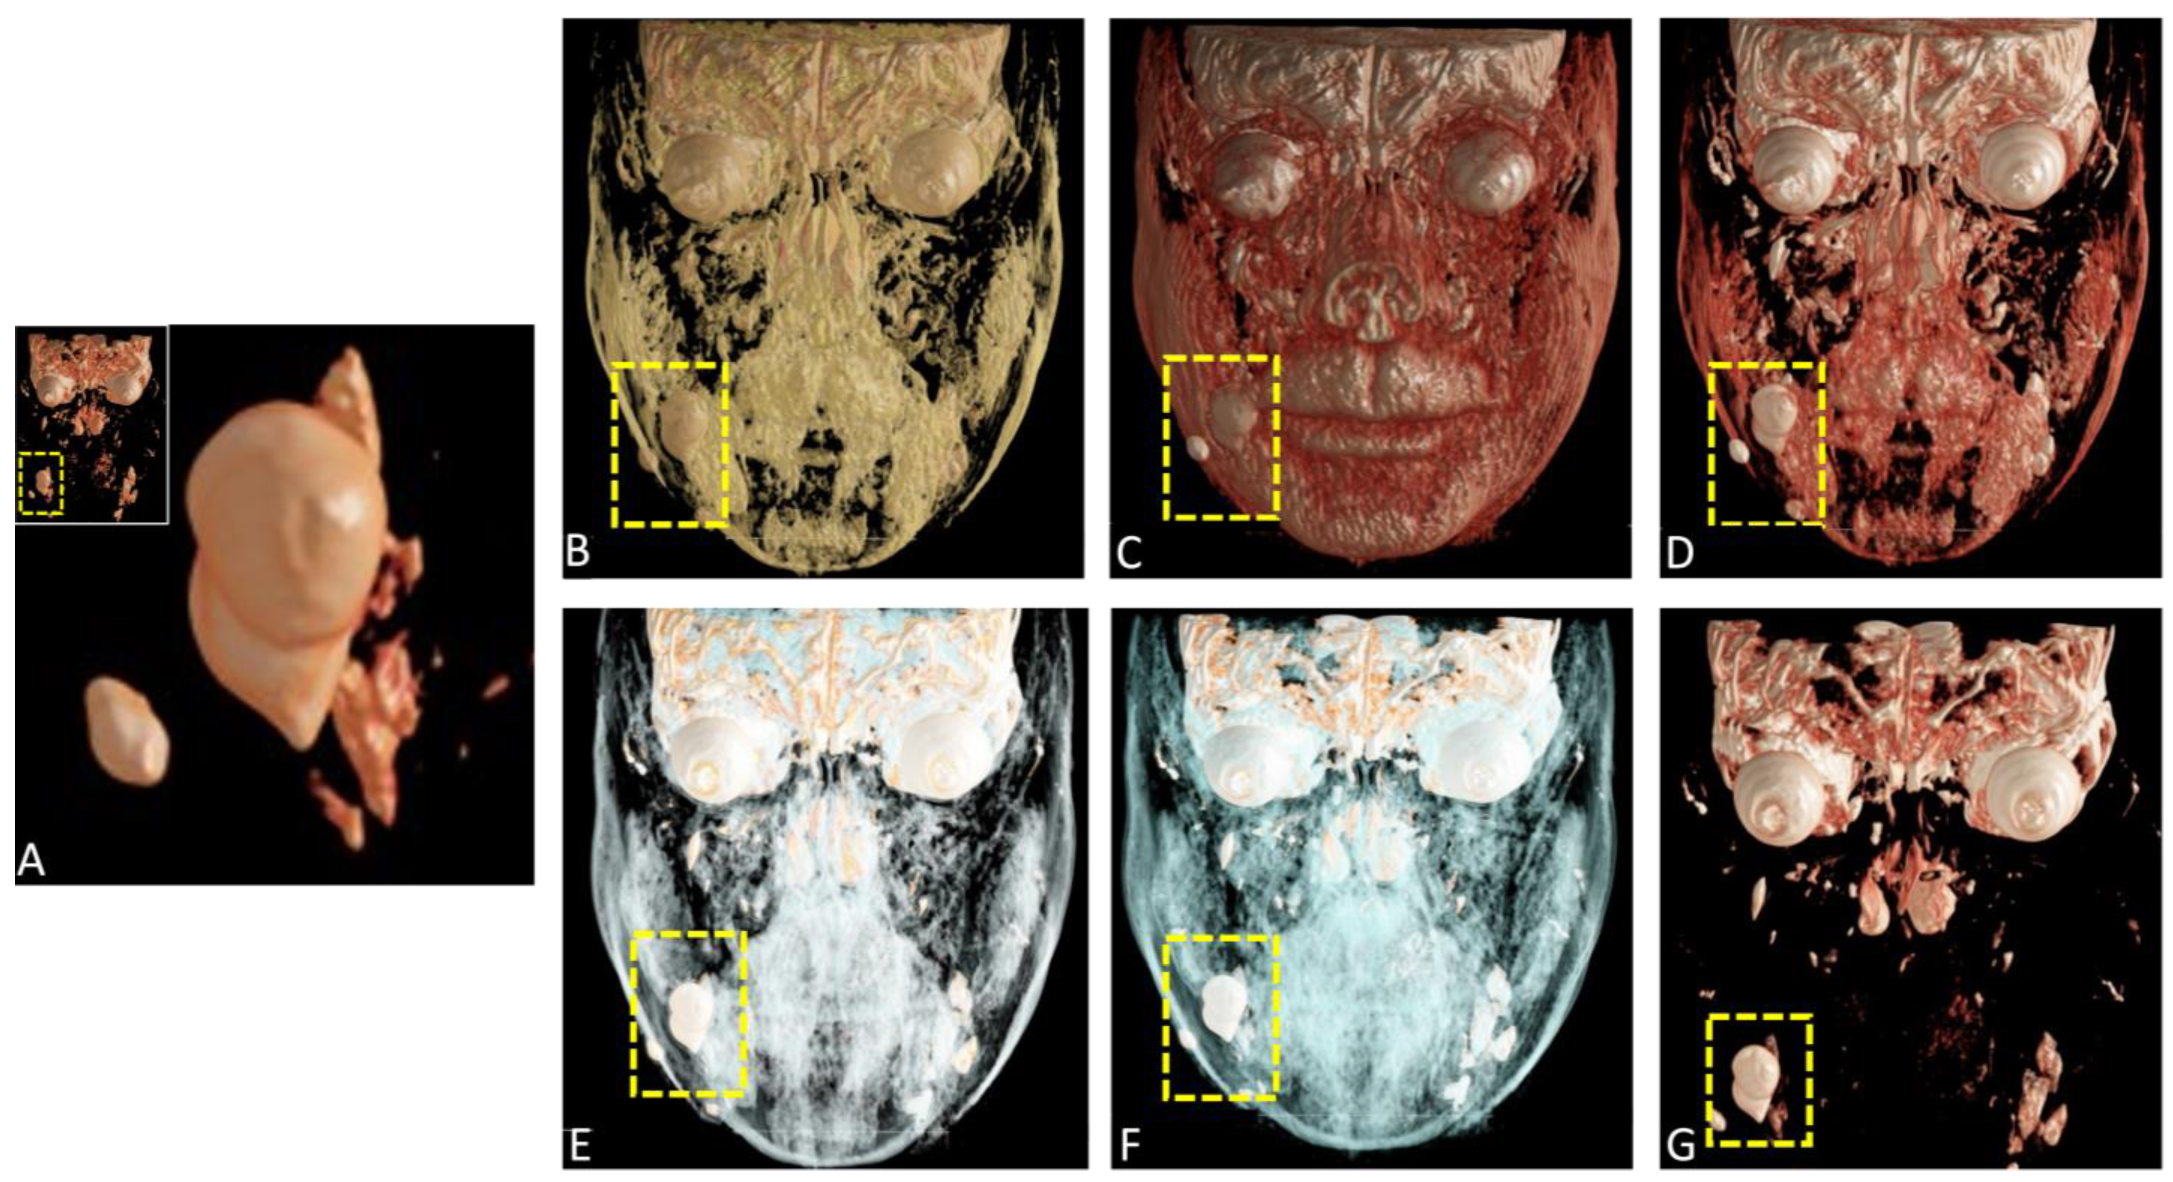

Preoperative coronal cinematic rendering (CR) reconstructions from magnetic resonance imaging (MRI) datasets using a variety of presets (A–G). The integration of various presets further optimizes the representation of superficial structures, contributing to improved diagnostic accuracy and aiding in surgical planning.